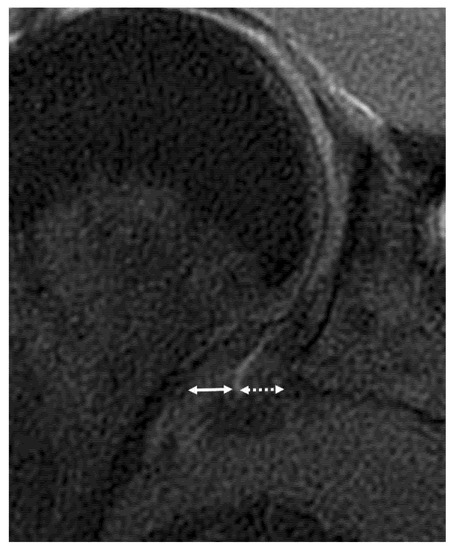

2.5. Image Analysis

- 1: normal homogenous low signal intensity

- 2: partial or foci of signal hyperintensity

- 3: global signal hyperintensity

- 4: linear hyperintensity of the peri-articular soft tissues